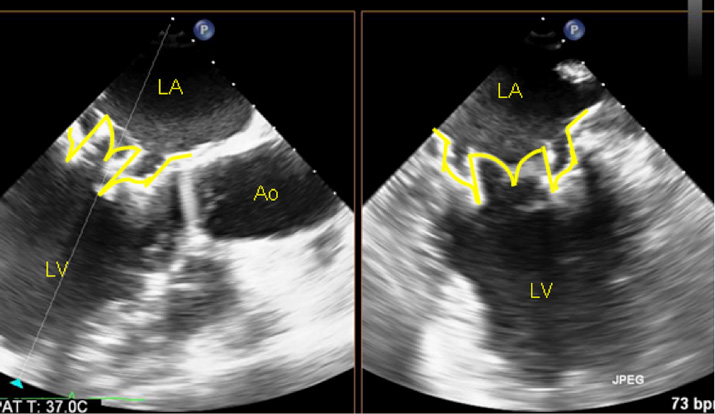

Η βαλβίδα TWELVE όπως απεικονίζεται με το υπερηχοκαρδιογράφημα.